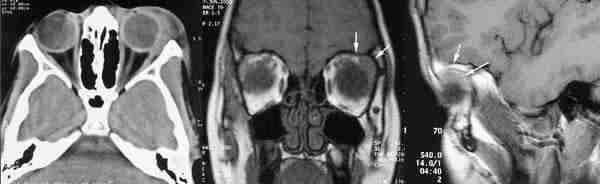

El TC y la RNM delimitan la extensión y características de la invasión de

canal óptico y quiasma, teniendo la RNM más definición.

El TC demuestra hiperóstosis y calcificaciones anormales intratumorales. La

RNM con gadolinio delimita claramente su extensión pudiendo definirse el nervio

óptico rodeado por la tumoración. Es la técnica de elección cuando el

meningioma está confinado en la órbita y tiene buena agudeza visual (200).